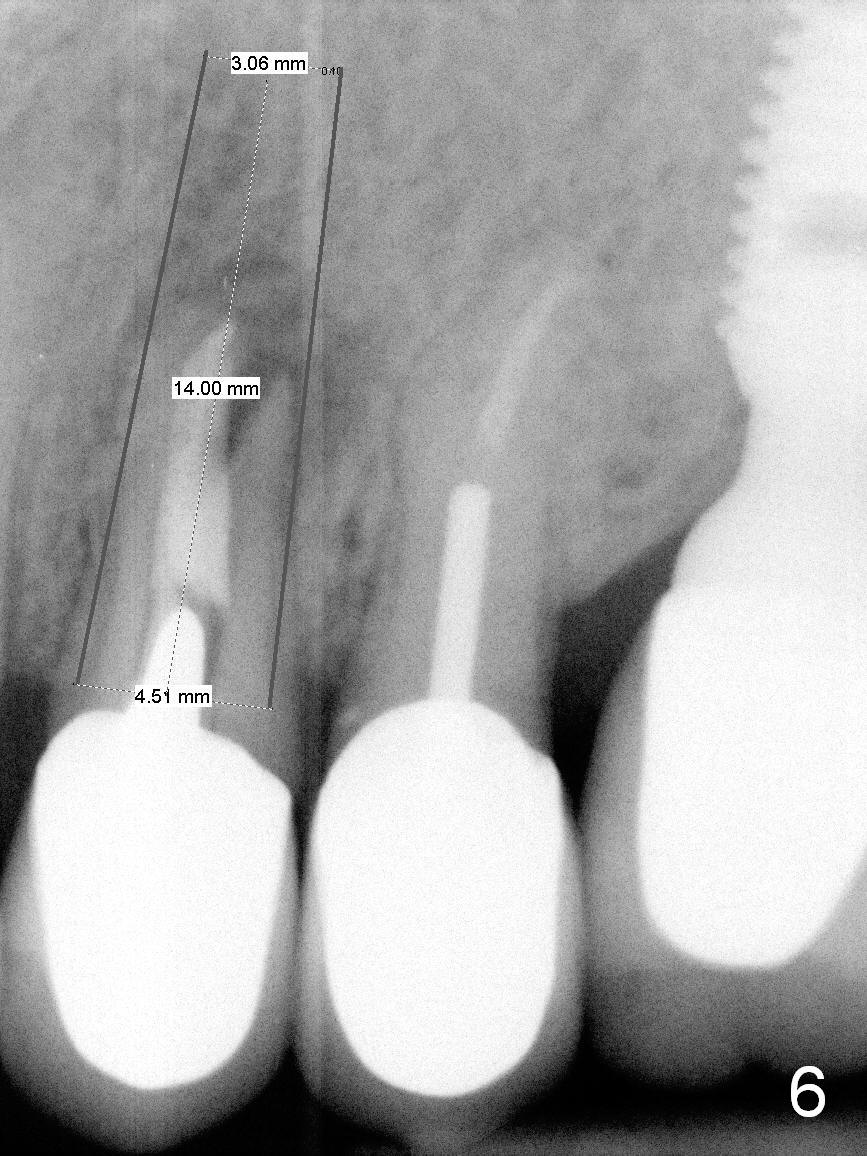

A 4.5x14 mm bone-level or 4.5x17 mm tissue-level implant appears to be appropriate for the site according to the PA (Fig.6,7).  CBCT shows that there is enough bone to place a 4.5x20 mm tissue-level implant (Fig.8).  This is more appropriate, considering the large radiolucency (Fig.5), the age of the patient (possibly osteoporosis), and the maxilla (bone softer than that of the mandible).  The implant will be supported by approximately 8 mm solid bone apically (Fig.8).

In addition, osteotomy will be under prep.  The depth of a 2 mm pilot drill, 2.5 mm and 3 mm reamers will be 20 mm, 17 mm and 14 mm, respectively.  A 4.5x20 mm tap will be inserted 17 mm before placing the corresponding implant.  Intraop PAs are to be taken following the pilot drill, tap and implant.